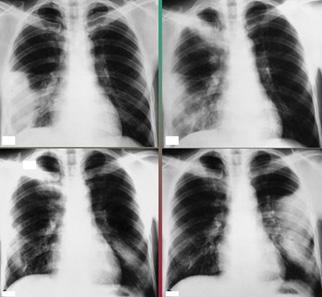

Tenemos el score de Killip que establece una clasificación clínica radiológica al ingreso del paciente con SCACEST.

Clase Hallazgos clínicos Mortalidad I Sin signos ni síntomas de 0 a 5%

estertores o crepitantes, 3er ruido o aumento de PV

10 a 20%

Edema pulmonar 35 a 45%

Shock cardiogénico: hipotensión y vasoconstricción periférica

85 a 95%